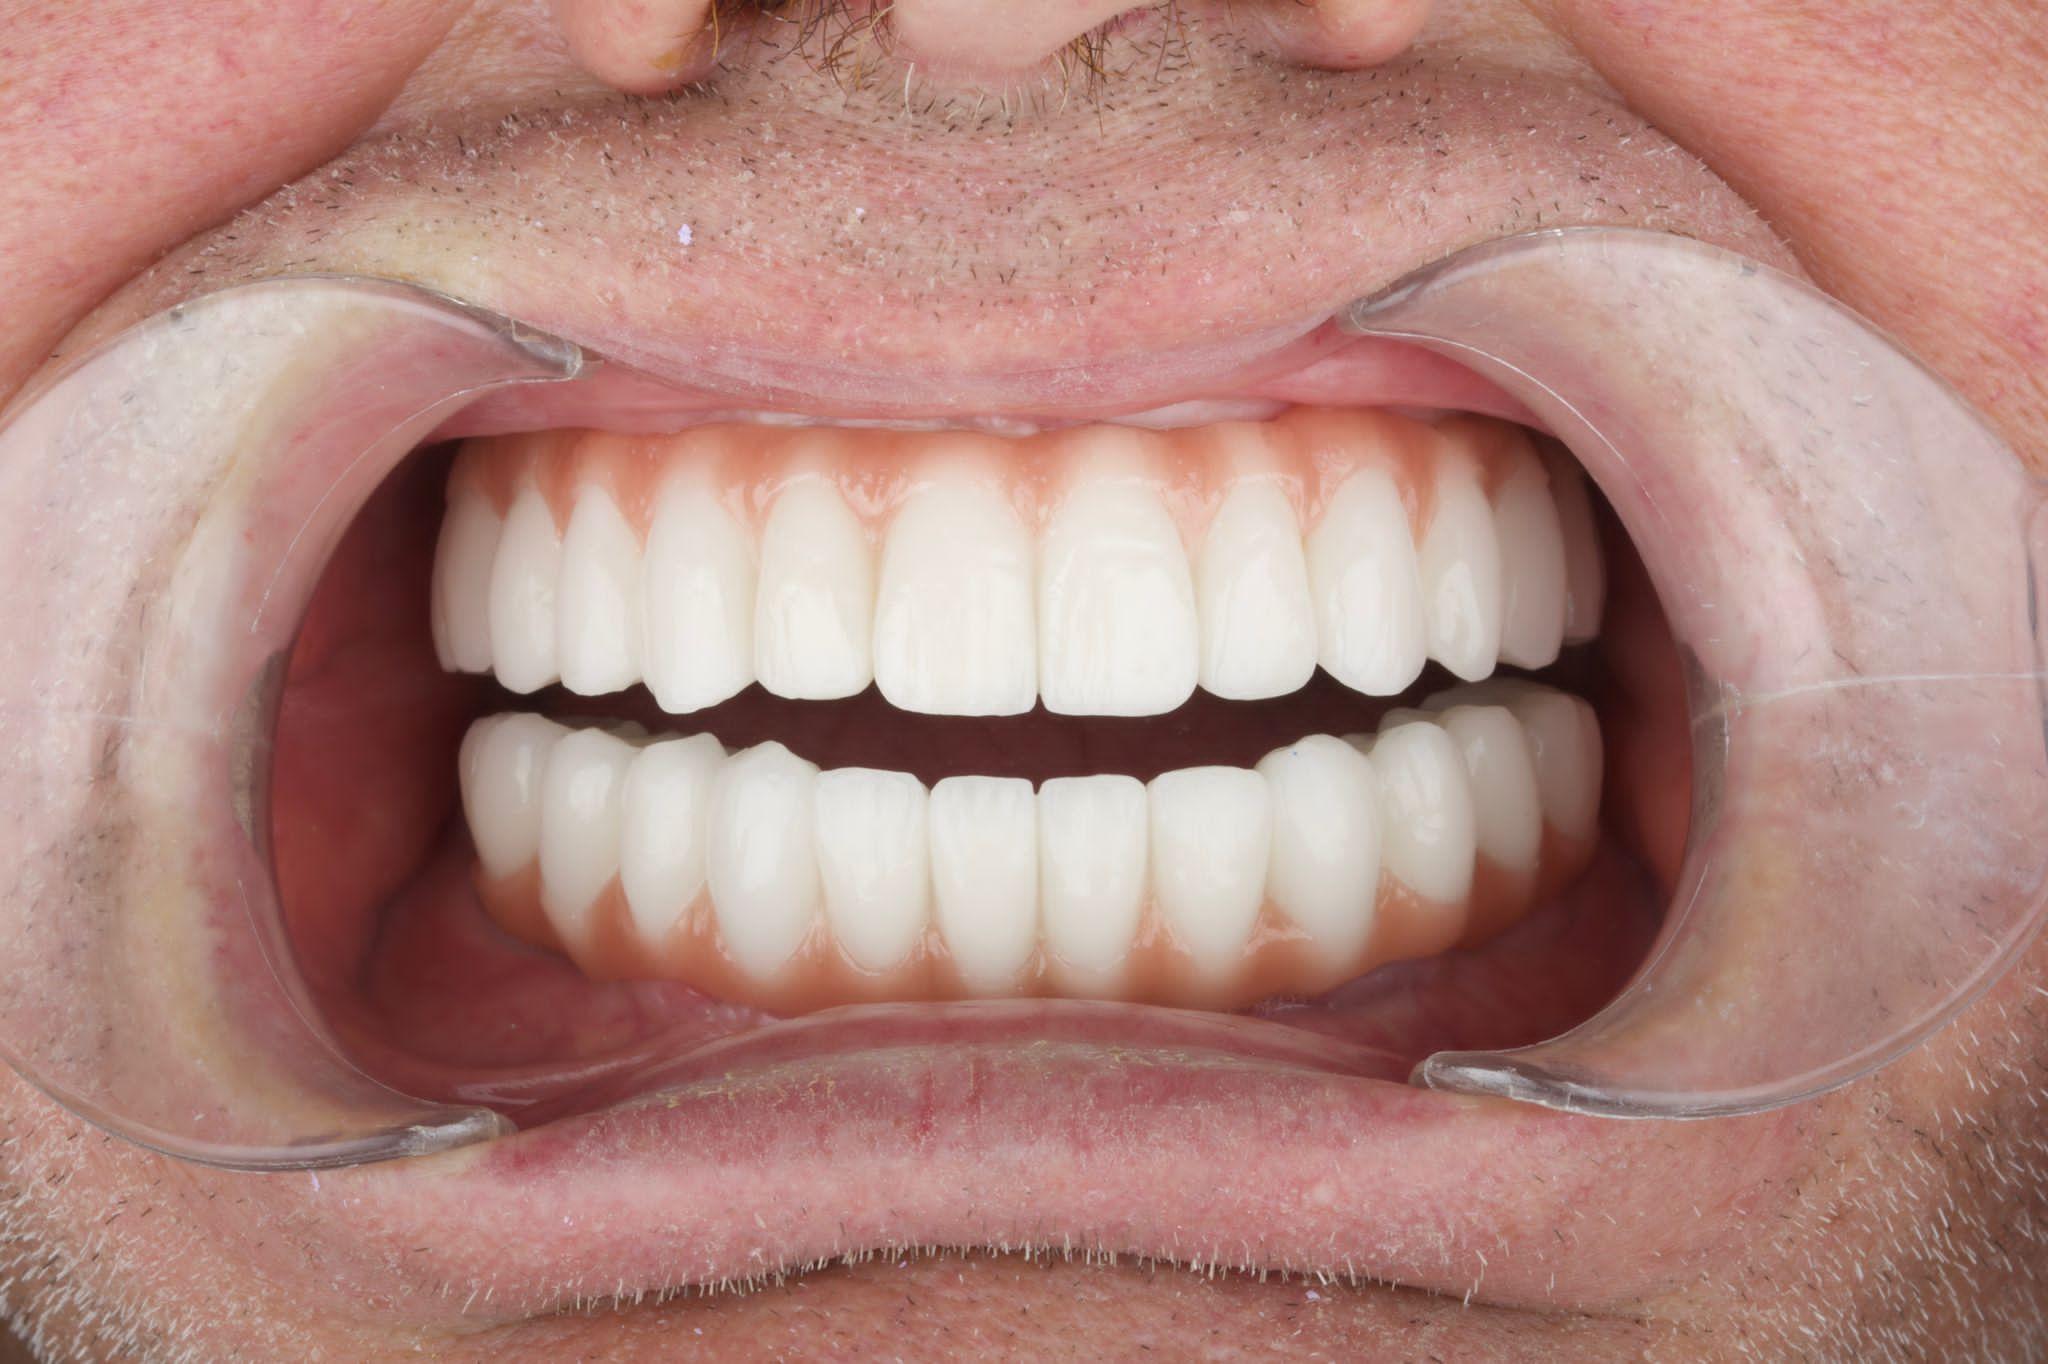

Before / After Results

Découvrez les transformations de nos patients